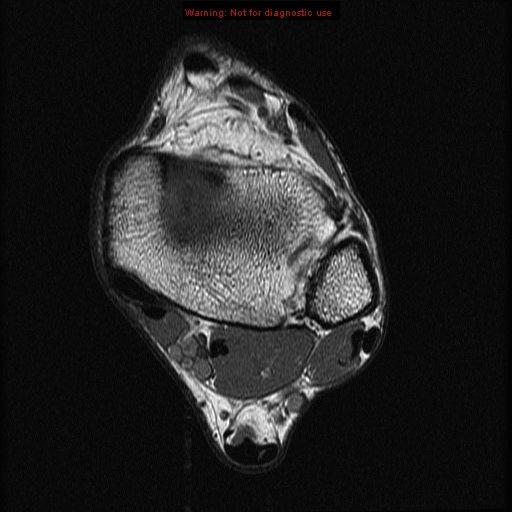

calcaneus

calcaneus lateral process of the talus

lateral process of the talus

tendon of peroneus longus achilles tendon

achilles tendon

extensor digitorum brevis muscle

extensor digitorum brevis muscle abductor hallucis muscle

abductor hallucis muscle

abductor digiti minimi